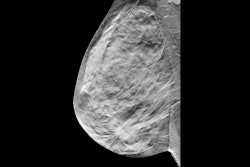

The guidelines outline when the use of PMRT is appropriate based on advances in diagnostics and clinical practice, and reviews best practices for delivering radiation after breast removal surgery, the organizations said.

The document provides information on appropriate target volumes, dosing, and treatment techniques. In addition, authors review treatment approaches aimed at reducing side effects and improving outcomes, including advances in radiation techniques, less invasive axillary surgery, and tailored systemic therapies.